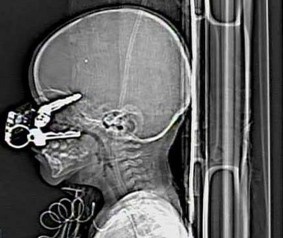

![]() |

| Các bác sĩ đã rất kinh ngạc khi tiếp nhận trường hợp của một em bé 17 tháng tuổi, với những chìa khóa gây thương tích nghiêm trọng ở giác mạc. |